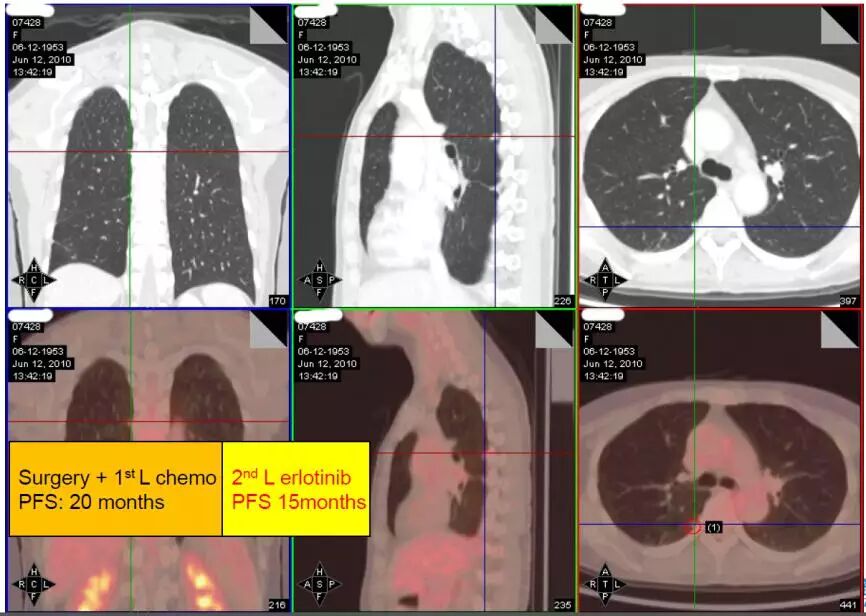

2010年6月12日,出现了新的病灶,CEA为51.33ng/ml。

图2.手术+一线化疗的PFS为20个月、二线厄洛替尼治疗PFS为15个月

这时面临选择,是切换成双药化疗?另一种EGFR-TKI治疗?继续厄洛替尼治疗?继续厄洛替尼治疗+局部治疗?重新检测T790M?